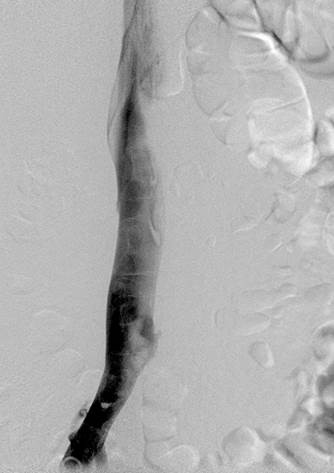

Venograma de la pierna izquierda donde se muestra un trombo oclusivo en las venas profundas más visualizadas.